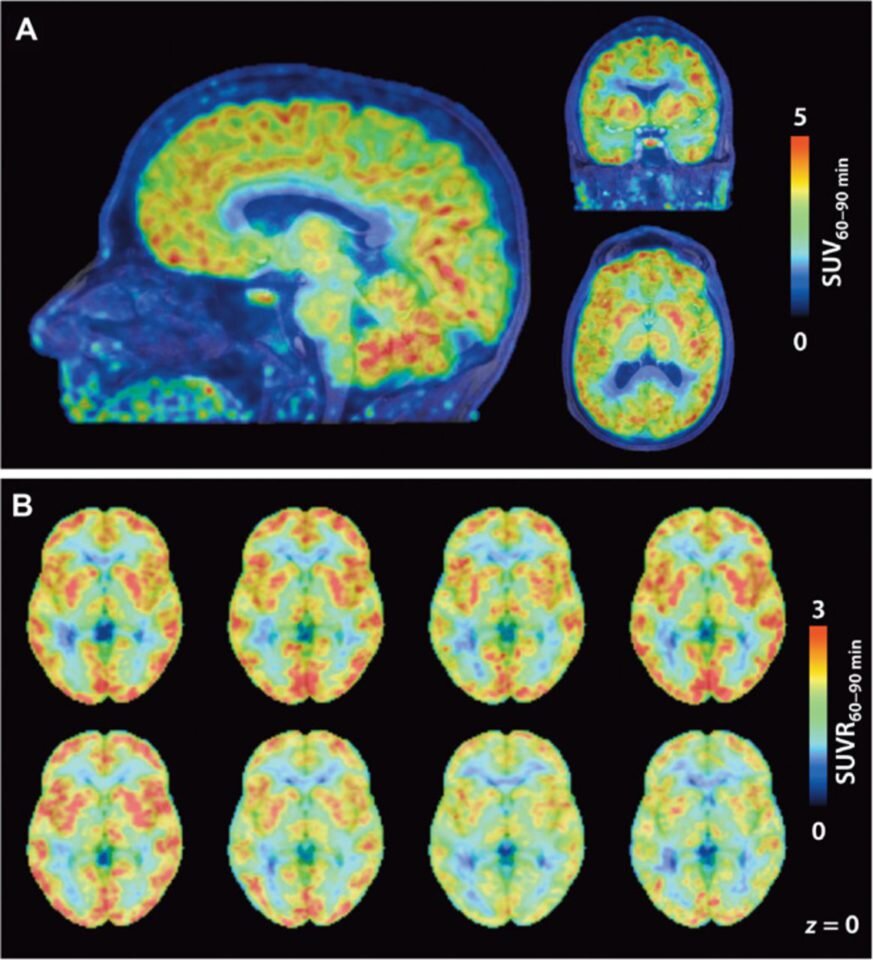

Credit:Hsiao-Ying Wey et al, Science Translational Medicine

Сначала исследователи провели эксперименты на грызунах и приматах, а затем приступили к людям. Восемь добровольцев принимали мартиностат и немедленно ложились в томограф ПЭТ. Оказалось, что в сером веществе  экспрессия HDAC почти вдвое выше, чем в белом, а в самом сером веществе максимальный уровень наблюдался в путамене (скорлупе, части чечевицеобразного ядра) и мозжечке, которые отвечают за обучение и движение, а минимальный — в гиппокампе и миндалине, ответственные за память, принятие решений и эмоции.